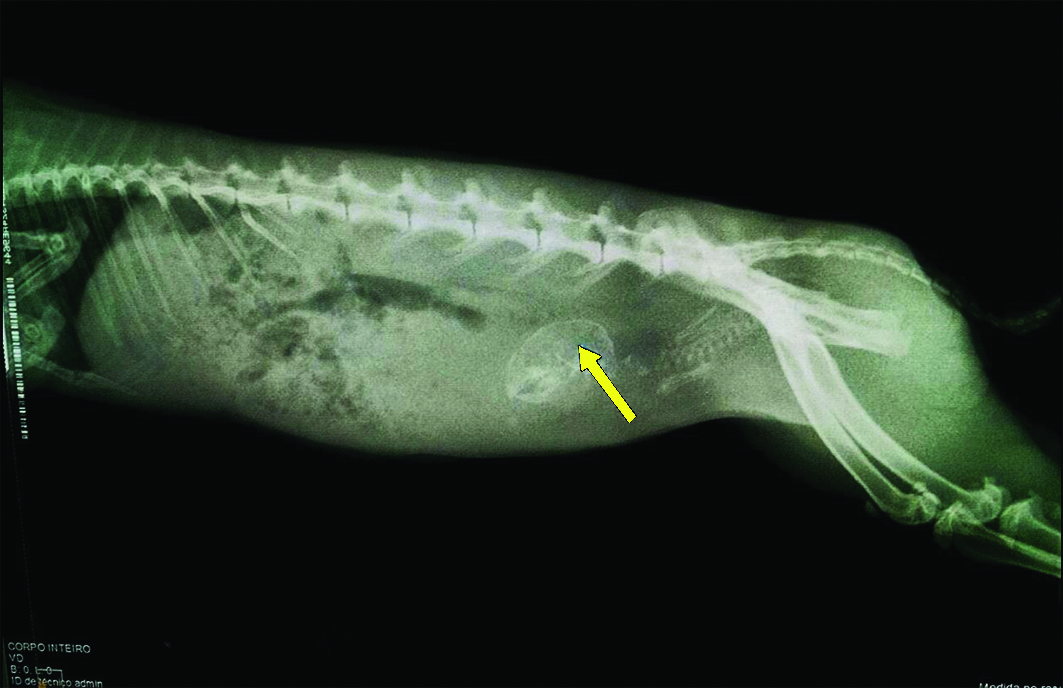

Na palpação abdominal, havia presença de estrutura de consistência firme na região do útero. Com diagnóstico presuntivo de distocia, realizou-se uma incidência radiográfica lateral, observando-se o esqueleto de um feto no interior do útero (Figura 2), assim como a presença de linhas de crescimento nas epífises ósseas dos membros pélvicos da mãe. Como a proprietária tinha pouco recurso para custear os gastos com o animal, não se realizou exame ultrassonográfico.

O exame radiográfico foi imprescindível para confirmar o diagnóstico, indicando a presença de feto retido no interior do útero materno. Os exames de imagem indicados nos casos de distocia na literatura são a radiografia e a ultrassonografia 11,12. No presente estudo utilizou-se apenas o exame radiográfico, pela disponibilidade, o que permitiu a confirmação da suspeita clínica, não sendo realizado o exame ultrassonográfico, em função da falta de recursos da proprietária.